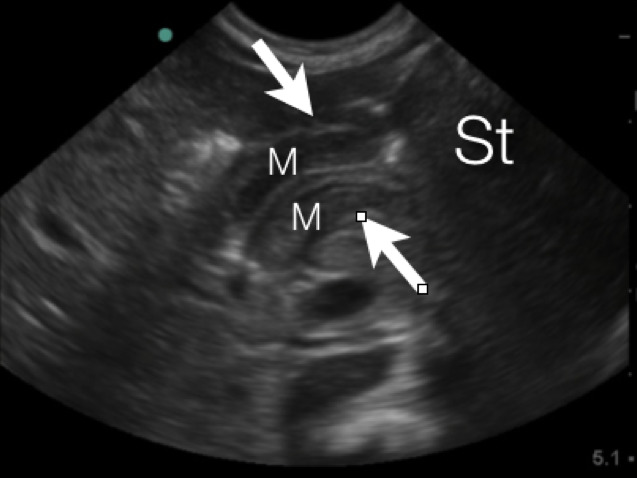

- Figure 4a. Long axis view of the pyloric musle (M) highlighted by white arrows at the distal end of the stomach (St)

- In between the pyloric muscles is the hyperechoic pyloric channel made up of gastric mucosa.

- Figure 4b.Highlighted pyloric channel made up of gastric mucosa